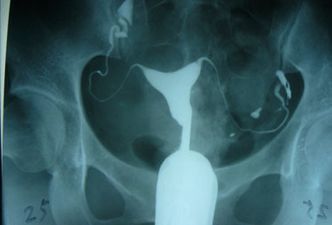

输卵管造影是通过导管向宫腔及输卵管注入造影剂,进行X线透视及摄片,根据造影剂在输卵管及盆腔内的显影情况了解输卵管是否通畅、阻塞部位及宫腔形态。输卵管造影不但能直观地了解输卵管是否通畅及其形态、阻塞的部位,而且能观察子宫腔的大小、形态、有无畸形及有无宫腔粘连或占位性病变,是不孕患者必备的一项检查。